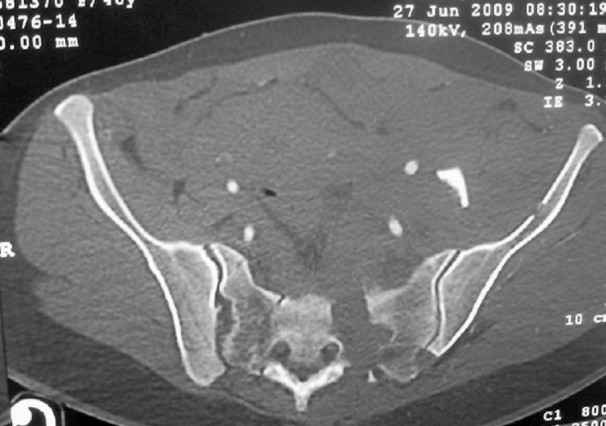

General condition is fine except for an intractable pelvic pain, no associated injuries (only ankle fracture), no sciatic nerve injury.

The soft tissues are also in mild condition, buttock hematoma and probably a Morel-Lavalle. I send some more CT images. There are some conminution in the posterior column (I don’t have images now). The patient is scheduled for surgery next Monday. The plan is percutaneous sacral fixation and then ilioinguinal approach .